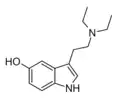

| 5-HO-DET | artificial | 5-OH | CH2CH3 | CH2CH3 | 5-hydroxy-N,N-diethyltryptamine | 14009-42-8 |